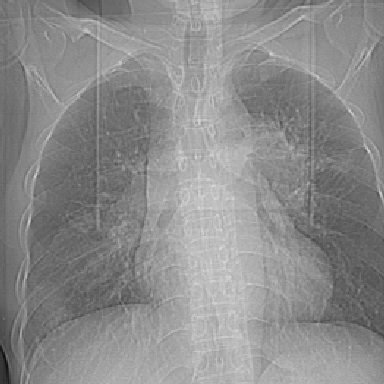

以下是引用zjzjr在2007-3-23 17:24:00的发言:[br]双侧肺门淋巴结明显肿大,以左侧为著,支气管受压变窄,肺内可见结节状及絮状高密度影,边缘模糊.考虑淋巴瘤肺内浸润.